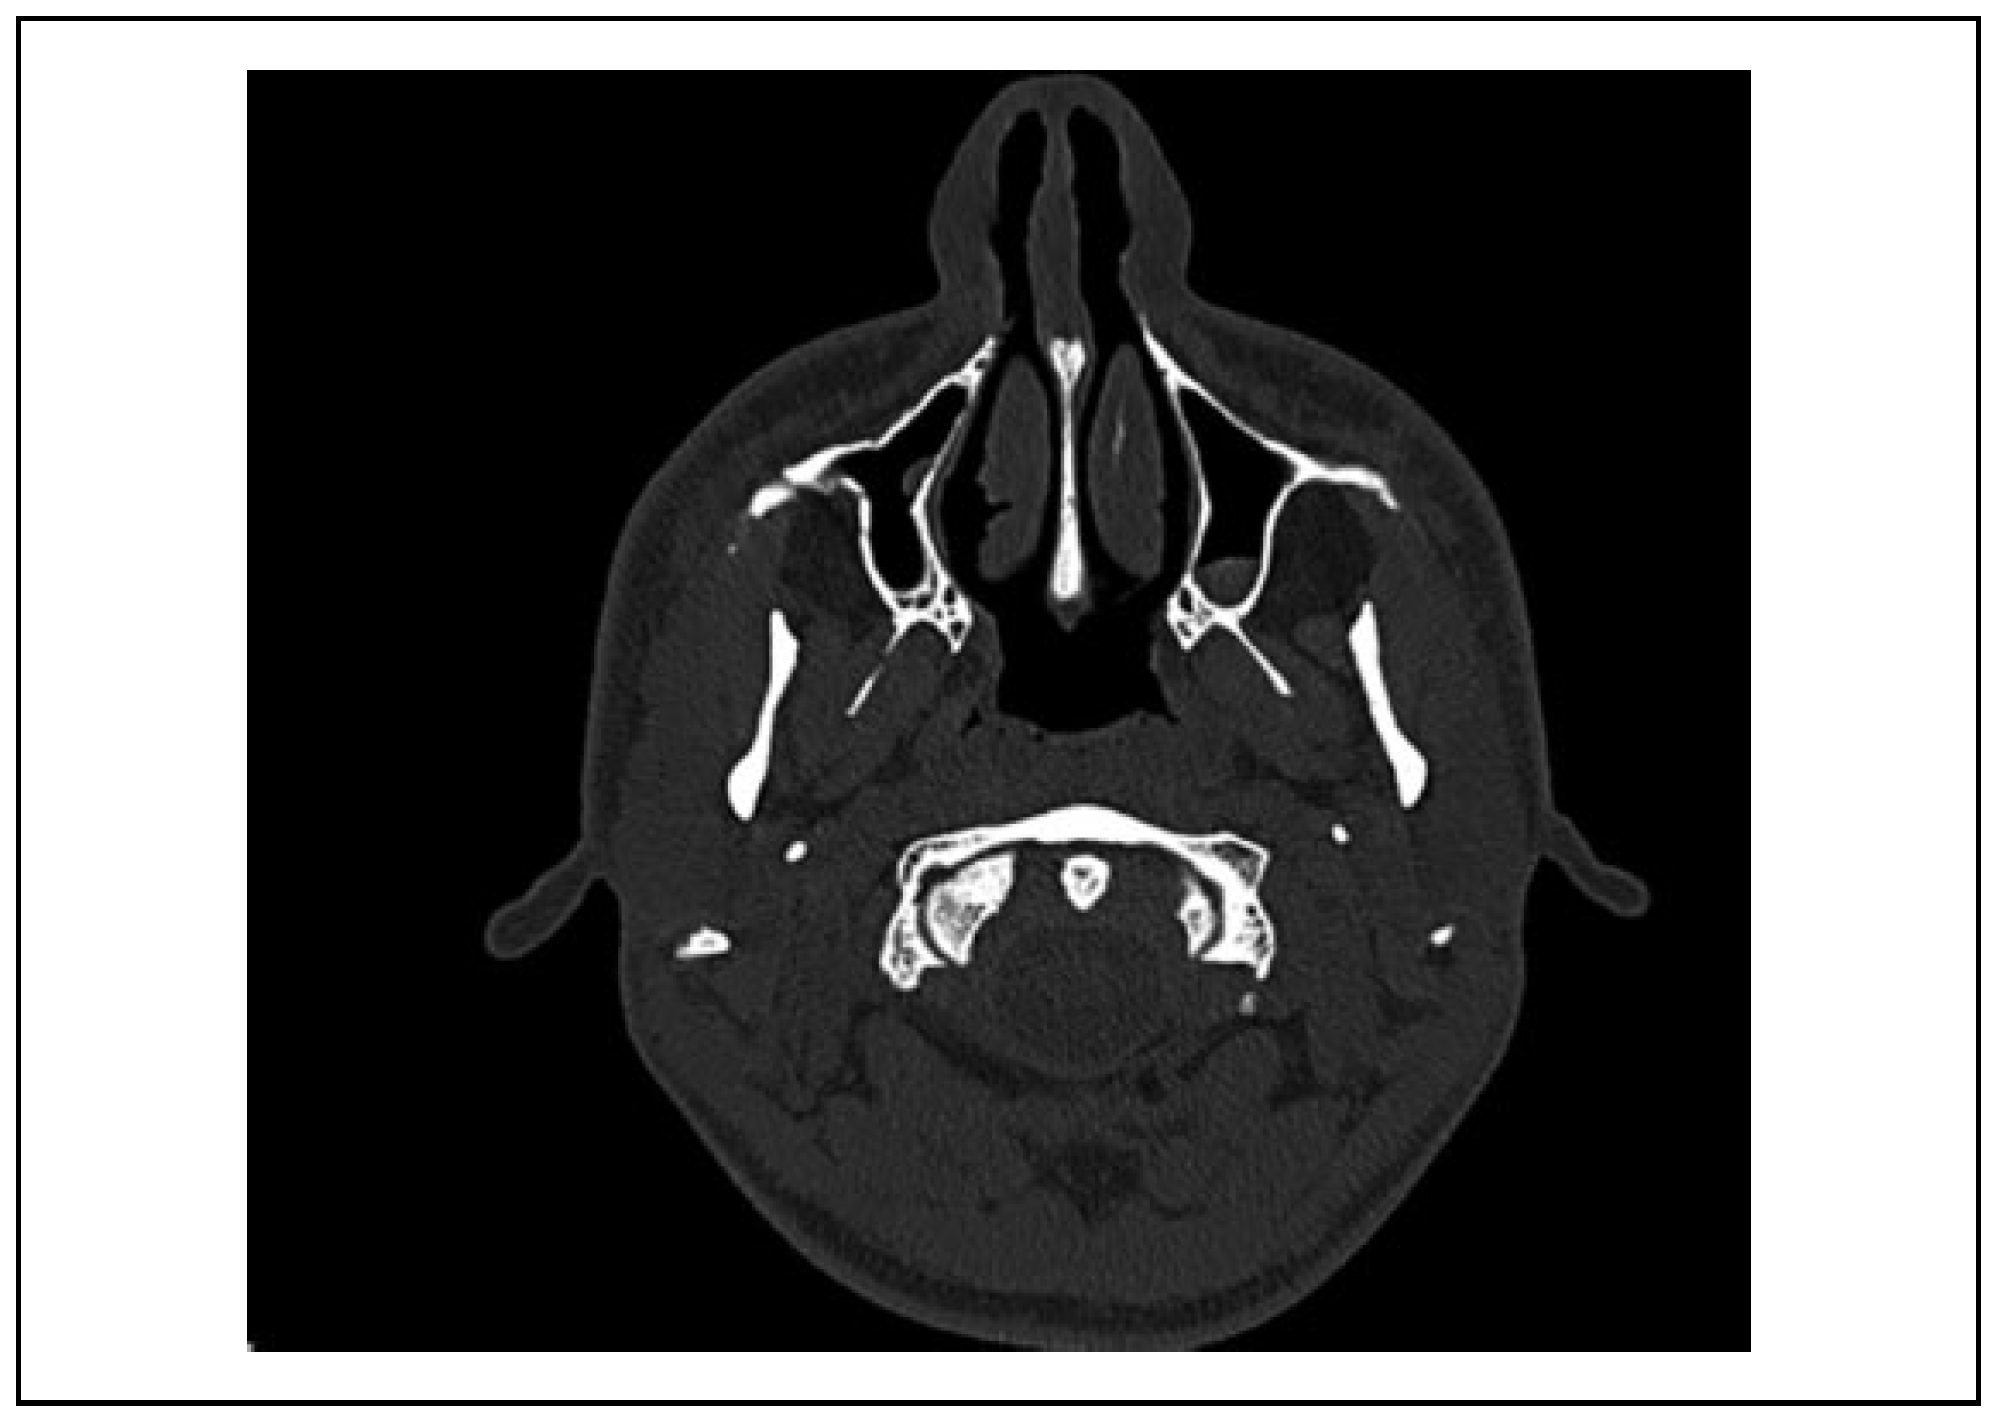

Case 2

Case 3